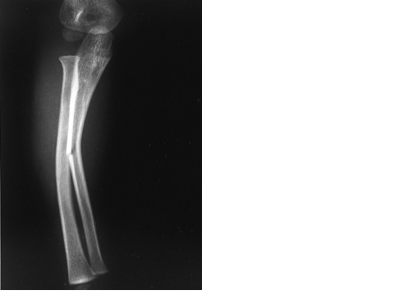

Green Stick Fracture

In young soft bone where the bone breaks a little